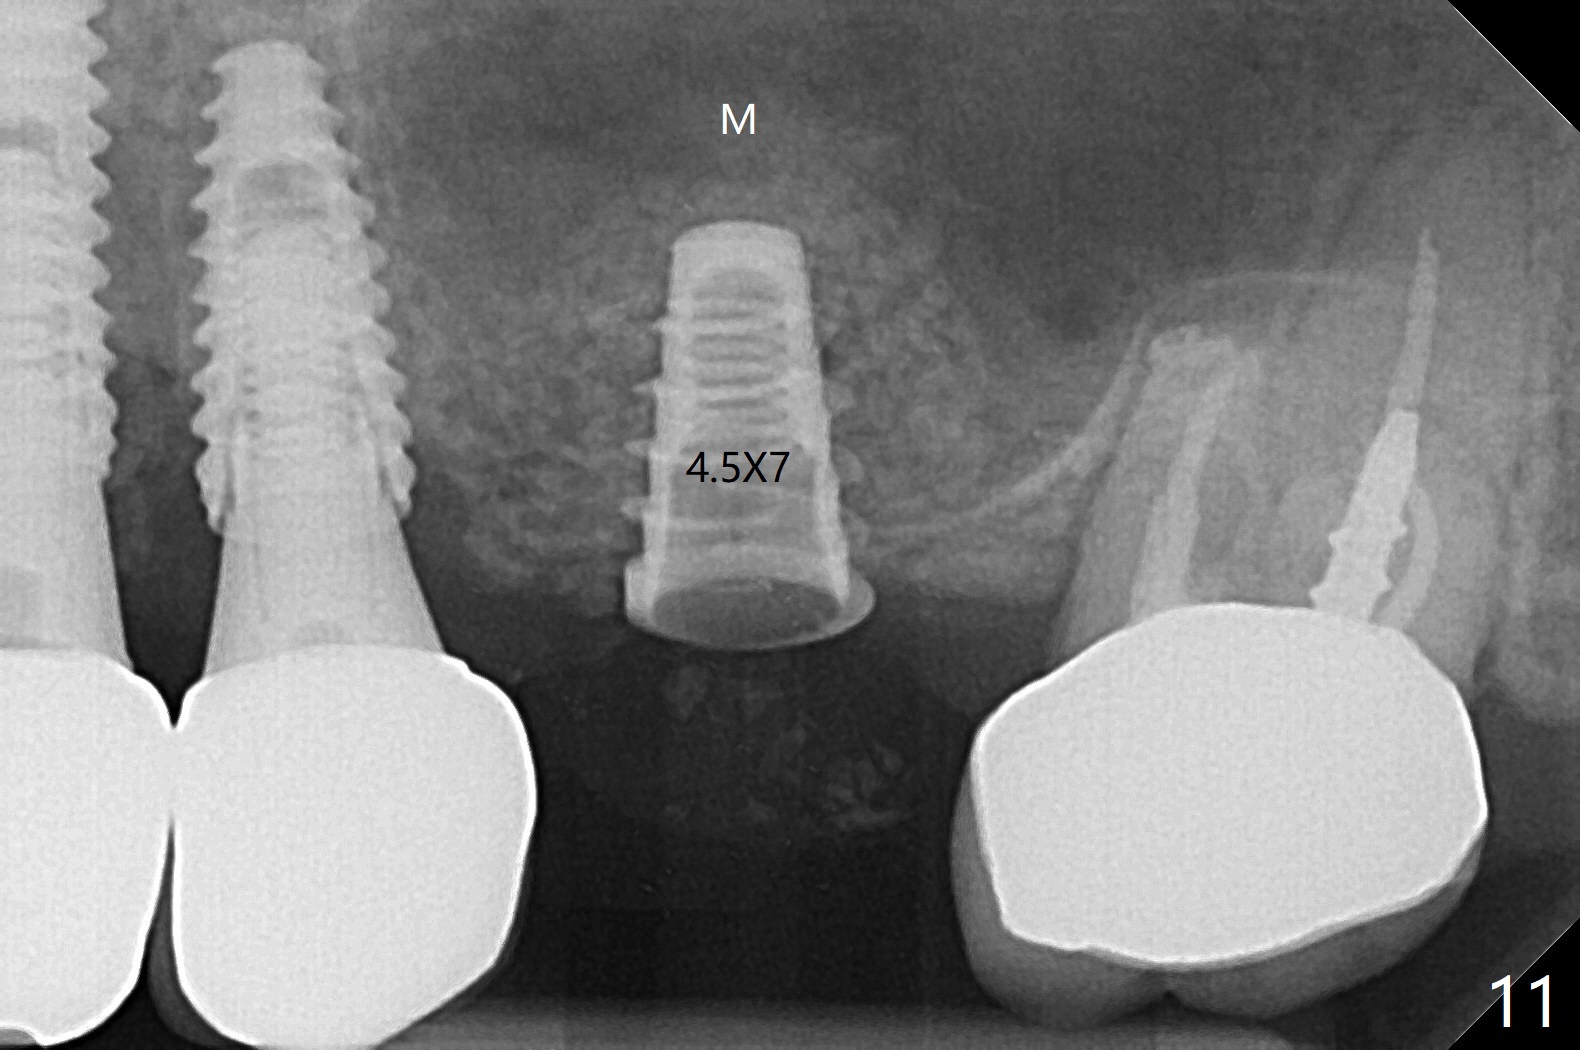

A 68-year-old timid woman is considering implant at #14 twenty months post cementation of #13 and 14 crown (Fig.1). Because of the narrow buccopalatal width (Fig.2 CT coronal section, B: buccal), a 4 mm implant (blue line) seems to be appropriate for the site (Fig.1). After crestal incision and flap reflection, a diamond round bur is used to thin the sinus floor until the bluish membrane is barely visible. An osteotome (Magic Sinus Lifter) is used for penetration. Water lift will be conducted if necessary, considering the already thickened sinus membrane (Fig.3 (CT sagittal section) M). Insert the first PRF membrane, followed by bone graft (not too sticky) repeatedly. Use sensor 1 to confirm lift degree. Try a 4x7 mm dummy FC to test stability. Place a definitive one (probably Magicore) if indicated. Use a second PRF membrane before closure of the wound. After nearly 15 month consideration (including coronovirus), the patient decides to get it done. With incision (Fig.4) and Marking Drill (Fig.5, the sinus membrane barely visible in the middle of the osteotomy (dimple, Fig.6 (black triangle)), the sinus floor does not break upon Magic Sinus Lifter). Later the patient complains of discomfort with tapping. In fact Magic Drill (similar to trephine bur, Fig.7) is used to break into the sinus without membrane perforation (Fig.8). Remember the thick membrane (Fig.2,3). In fact the fractured fragment is attached to the membrane (Fig.9 red lines, green sticky fracture). A small curette is used to further separate the membrane from the bony wall (Fig.10) before insertion of a small piece of PRF and sticky bone. When a 4.5x7 mm dummy implant is incompletely placed with stability (<10 Ncm), the membrane is stretched over the bone graft (Fig.11 M). After removal of the dummy, the major remaining piece of PRF (from 9 cc vial) and more allograft are placed before inserting a definitive implant (same size) with 15 Ncm; still the used to be thick membrane remains intact and stretched (Fig.12 M). The implant is equicrestal buccal, while slightly supracrestal palatal. To prevent implant dislodgement into the sinus and bone graft, a final abutment is placed (Fig.12). The wound is closed with 4-0 PGA, perio glue and perio dressing. The latter dislodges 3 days postop. The wound seems to be healing. No dressing is reapplied.